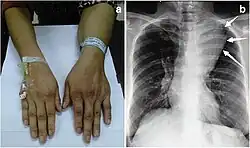

Large mediastinal angiolipoma | |

Angiolipoma typically manifests as many, painful subcutaneous nodules (solitary in only one-third of patients), most commonly originating in the upper limbs (of which the forearm accounts for around two thirds), trunk, and lower limbs.[3][4] These lesions are well-defined, usually measuring less than 4 cm.[5]